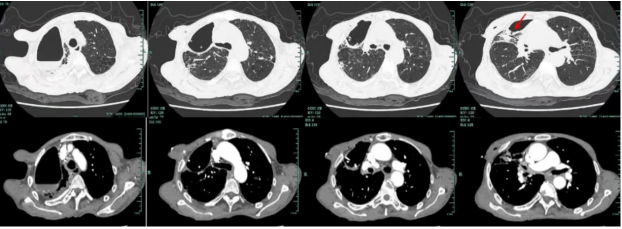

• 胸部增强CT(2023-05-07):红箭头所示为瘘口胸膜残腔相通3

图片

3  胸部增强CT(2023-05-07)